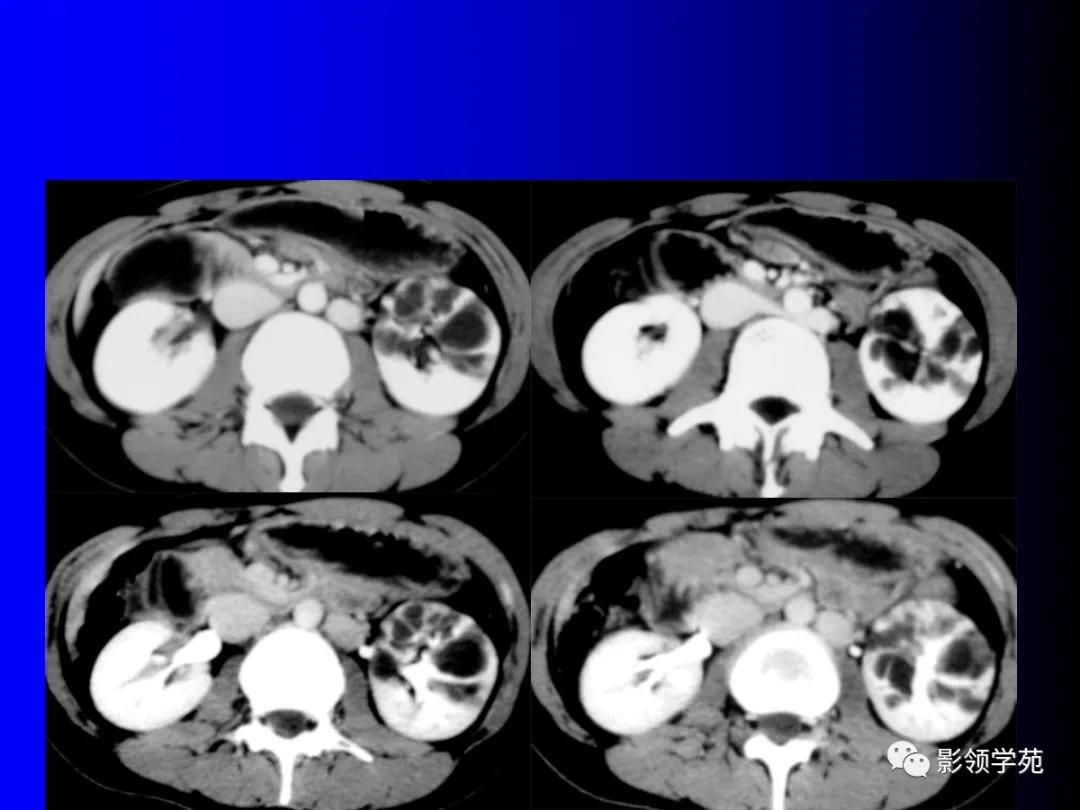

12、肾癌囊变和多房囊性肾癌

肾癌部分囊变易鉴别,少数需和感染性囊肿鉴别。

完全囊变常和肾囊肿混淆,少数不能鉴别。

多房囊性肾癌有完整分隔

2、囊性肾癌与肾癌囊变是两个不同的概念

前者是以囊性方式生长为主的肿瘤,后者是实体癌的广泛出血、坏死囊变而成。据Hartman等(1986)统计,囊性肾癌占肾癌总数的10%~15%。囊性肾癌的发病机制总体上还不很清楚,但认为可能是

(1)肿瘤出血,坏死,囊变;

(2)囊肿壁发生肿瘤;

(3)肿瘤阻塞肾小管形成囊肿并将肿瘤包绕于囊内;

(4)囊肿起源于近曲小管上皮细胞,部分以囊性方式生长,囊壁和囊间隔覆盖一层或多层肿瘤上皮细胞,呈乳头状在囊壁或向囊内生长。确切的机制还有待进一步研究。

3、囊性肾癌的CT表现

囊性肾癌的CT表现各异,根据本组影像结果显示,囊性肾癌主要有以下CT表现:

(1)平扫囊内平均CT值较单纯囊肿偏高,约15~20 HU,而单纯囊肿CT值 一般为10 HU以下。

(2)囊壁连续性中断,向邻近肾实质浸润低密度影。

(3)囊壁厚薄不均,有向囊内或囊外凸出的壁结节,可明显强化。

(4)部分囊壁模糊。

(5)平扫囊内密度不均者,增强扫描囊内可出现不均匀强化,CT值可达35 HU左右。

(6)冠状位后重建图像显示为不规则形囊性肿块。

(7)囊壁弥漫弧形钙化,良性单纯囊肿很少见,是否为囊性肾癌的典型征象尚有待商榷。